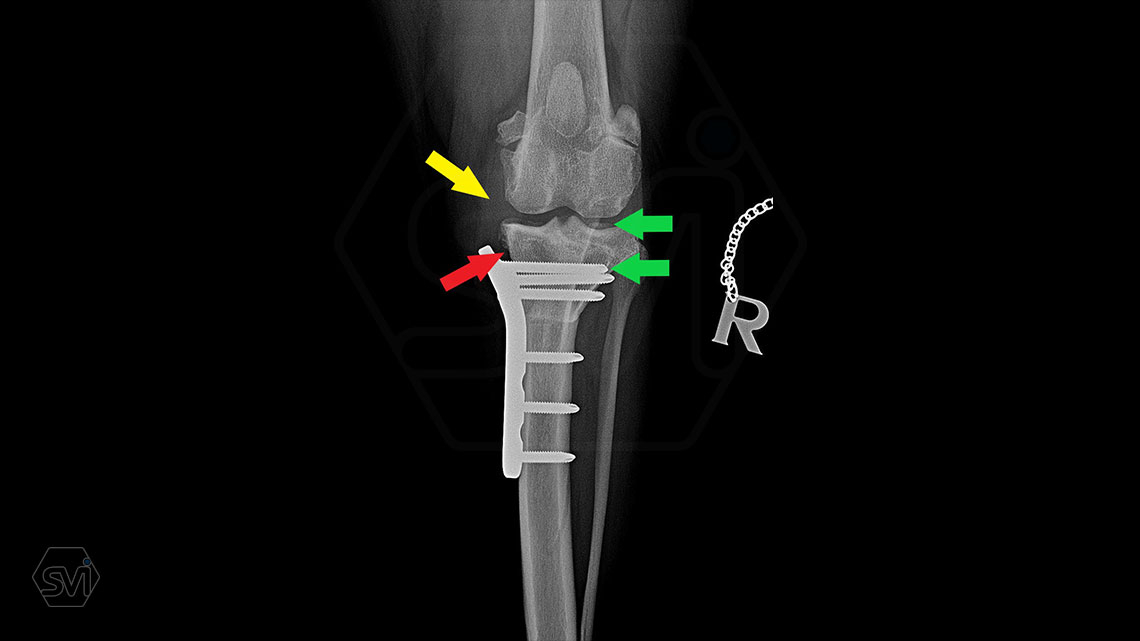

In the picture, the thickend med. collat. lig. marked with a yellow arrow, and the plate follows its shape, marked with a red arrow. The blood circulation in the tissues under the metal is not disturbed, which does not generate further pain and results faster bonehealing.

The screws were inserted in the proximal part with the monoaxial drill guide so the screws were parallel to the tibial plateau and we were sure during surgery that the screw would not penetrate the joint and the screw head would fit into the hole with maximum surface area!